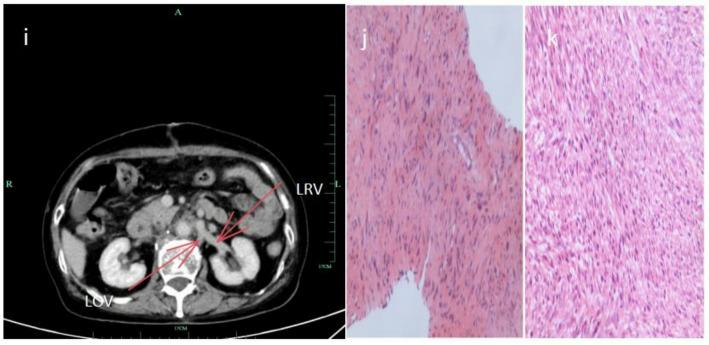

This case report describes a 75-year-old female patient who was admitted to the hospital with right lower abdominal pain and imaging studies suggesting a retroperitoneal mass and consideration of leiomyosarcoma. After the diagnosis was confirmed by imaging analysis combined with puncture biopsy, the patient received chemotherapy with adriamycin (75 mg/m²) and dacarbazine (200 mg/m²) to shrink the tumor once every 3 weeks for 4 cycles, which resulted in tumor shrinkage, and then underwent resection of the retroperitoneal leiomyosarcoma combined with resection of the inferior vena cava lesions. The retroperitoneal tumor involving the inferior vena cava (IVC) was completely resected without requiring IVC reconstruction during the surgical procedure. Final histopathological analysis confirmed the diagnosis of leiomyosarcoma. The patient demonstrated an uneventful postoperative recovery with no surgical complications, and subsequent follow-up evaluations revealed no evidence of disease recurrence, resulting in substantial improvement in the patient's quality of life on the basis of standardized oncology performance metrics.

本病例报告描述了一名75岁女性患者,因右下腹痛入院,影像学检查提示腹膜后肿块,考虑为平滑肌肉瘤。经影像分析结合穿刺活检确诊后,患者接受阿霉素(75mg/m²)和达卡巴嗪(200mg/m²)化疗,每3周一次,共4个周期以缩小肿瘤,肿瘤缩小后,接受了腹膜后平滑肌肉瘤切除术及下腔静脉病变切除术。手术过程中,累及下腔静脉(IVC)的腹膜后肿瘤被完全切除,无需进行IVC重建。最终组织病理学分析确诊为平滑肌肉瘤。患者术后恢复顺利,无手术并发症,随后的随访评估未发现疾病复发迹象,基于标准化肿瘤学性能指标,患者生活质量得到显著改善。